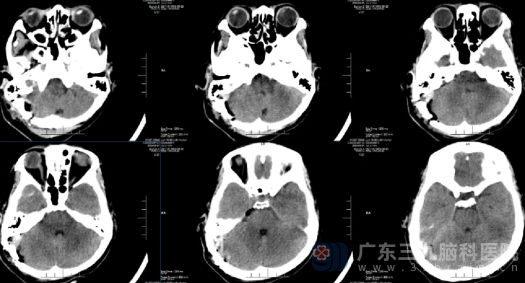

征得患者及家属同意后,患者在全麻下接受右侧桥小脑角区占位切除术联合三叉神经微血管减压术。手术采用右侧乙状窦后入路,显微镜下精准磨开内听道后壁,见黄白色肿瘤位于右侧桥小脑角区,质地中等。手术过程中精细分离血管,采用包膜内雕刻式切除方式,完整保护了面神经和耳蜗神经,全切肿瘤。术中还发现右侧小脑前下动脉分支压迫三叉神经,这正是为何患者会出现右上方牙痛症状的原因。医生垫入Teflon棉将血管与神经隔离,解决牙痛问题。

术后第一天,露露仅诉轻度头晕头痛。医生在神经系统检查时,也发现她的面部表情好,两侧鼻唇沟对称,面神经功能5级,完全无面瘫,亦无麻木感、无听力下降、耳鸣等特殊不适,四肢肌力V级,各项神经反射正常。